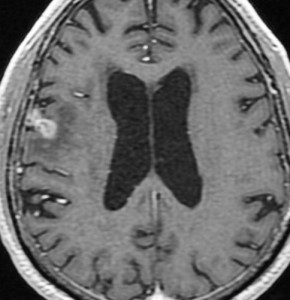

60代後半の患者さんで右前頭葉転移性脳腫瘍です。けいれん発作で発症しました。

定位放射線治療前

典型的な脳転移のMRIです。腫瘍は,リング状にガドリニウム増強され,内部が腫瘍壊死になっています。腫瘍周囲の脳浮腫がとても強いのが転移の特徴的画像所見(右側のT2強調画像)です。この転移巣に対して,35グレイ・5分割の定位放射線治療が加えられました。